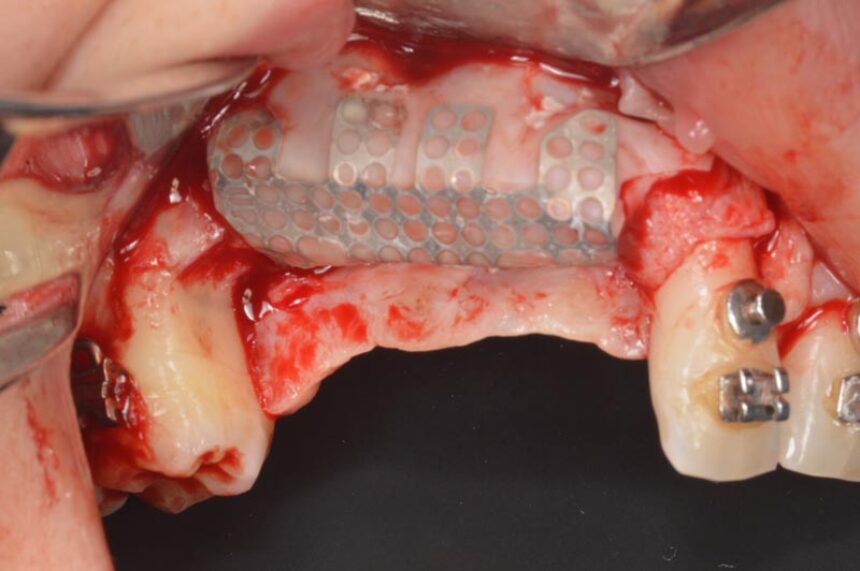

Οριζόντια και Κάθετη Αύξηση της Ακρολοφίας: χειρουργικό υπόβαθρο - χειρουργικές τεχνικές – απορροφήσιμες και μη-απορροφήσιμες μεμβράνες – λήψη οστικού μοσχεύματος από ενδο-στοματικά σημεία – βίντεο